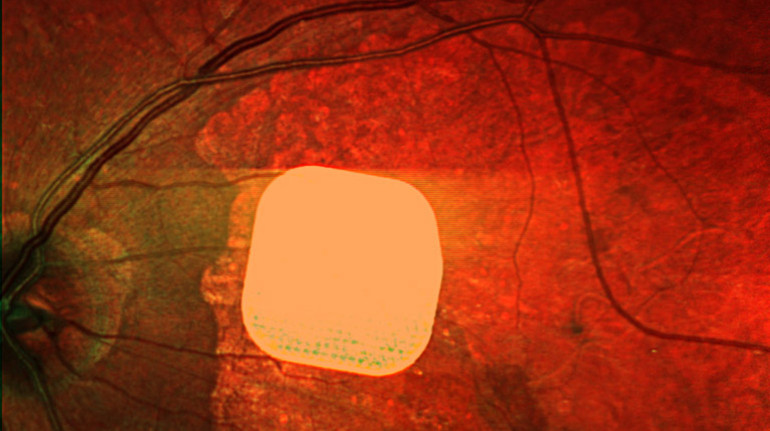

Photo: Science Corporation/PA

Prima implant is a 2×2 millimeter microchip that is surgically placed under the retina. During an operation lasting less than two hours, the patient is fitted with a device that then works together with augmented reality glasses.